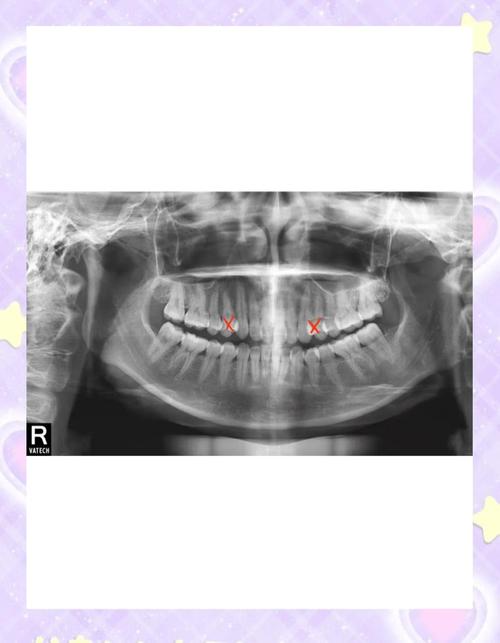

成年人矫正前需做好充分准备,与青少年相比,成年人口腔环境可能更复杂,比如存在牙周炎、龋齿、牙体缺损或修复体(假牙、烤瓷冠等),这些都需要先进行处理,若有牙周炎,需先进行系统治疗(如洁治、刮治),待牙周炎症控制、牙槽骨稳定后才能开始矫正,否则可能加重牙槽骨吸收,导致牙齿松动,还需通过X光片、CT等检查评估牙根情况、牙槽骨密度,以及颞下颌关节是否存在异常,排除矫正禁忌证。